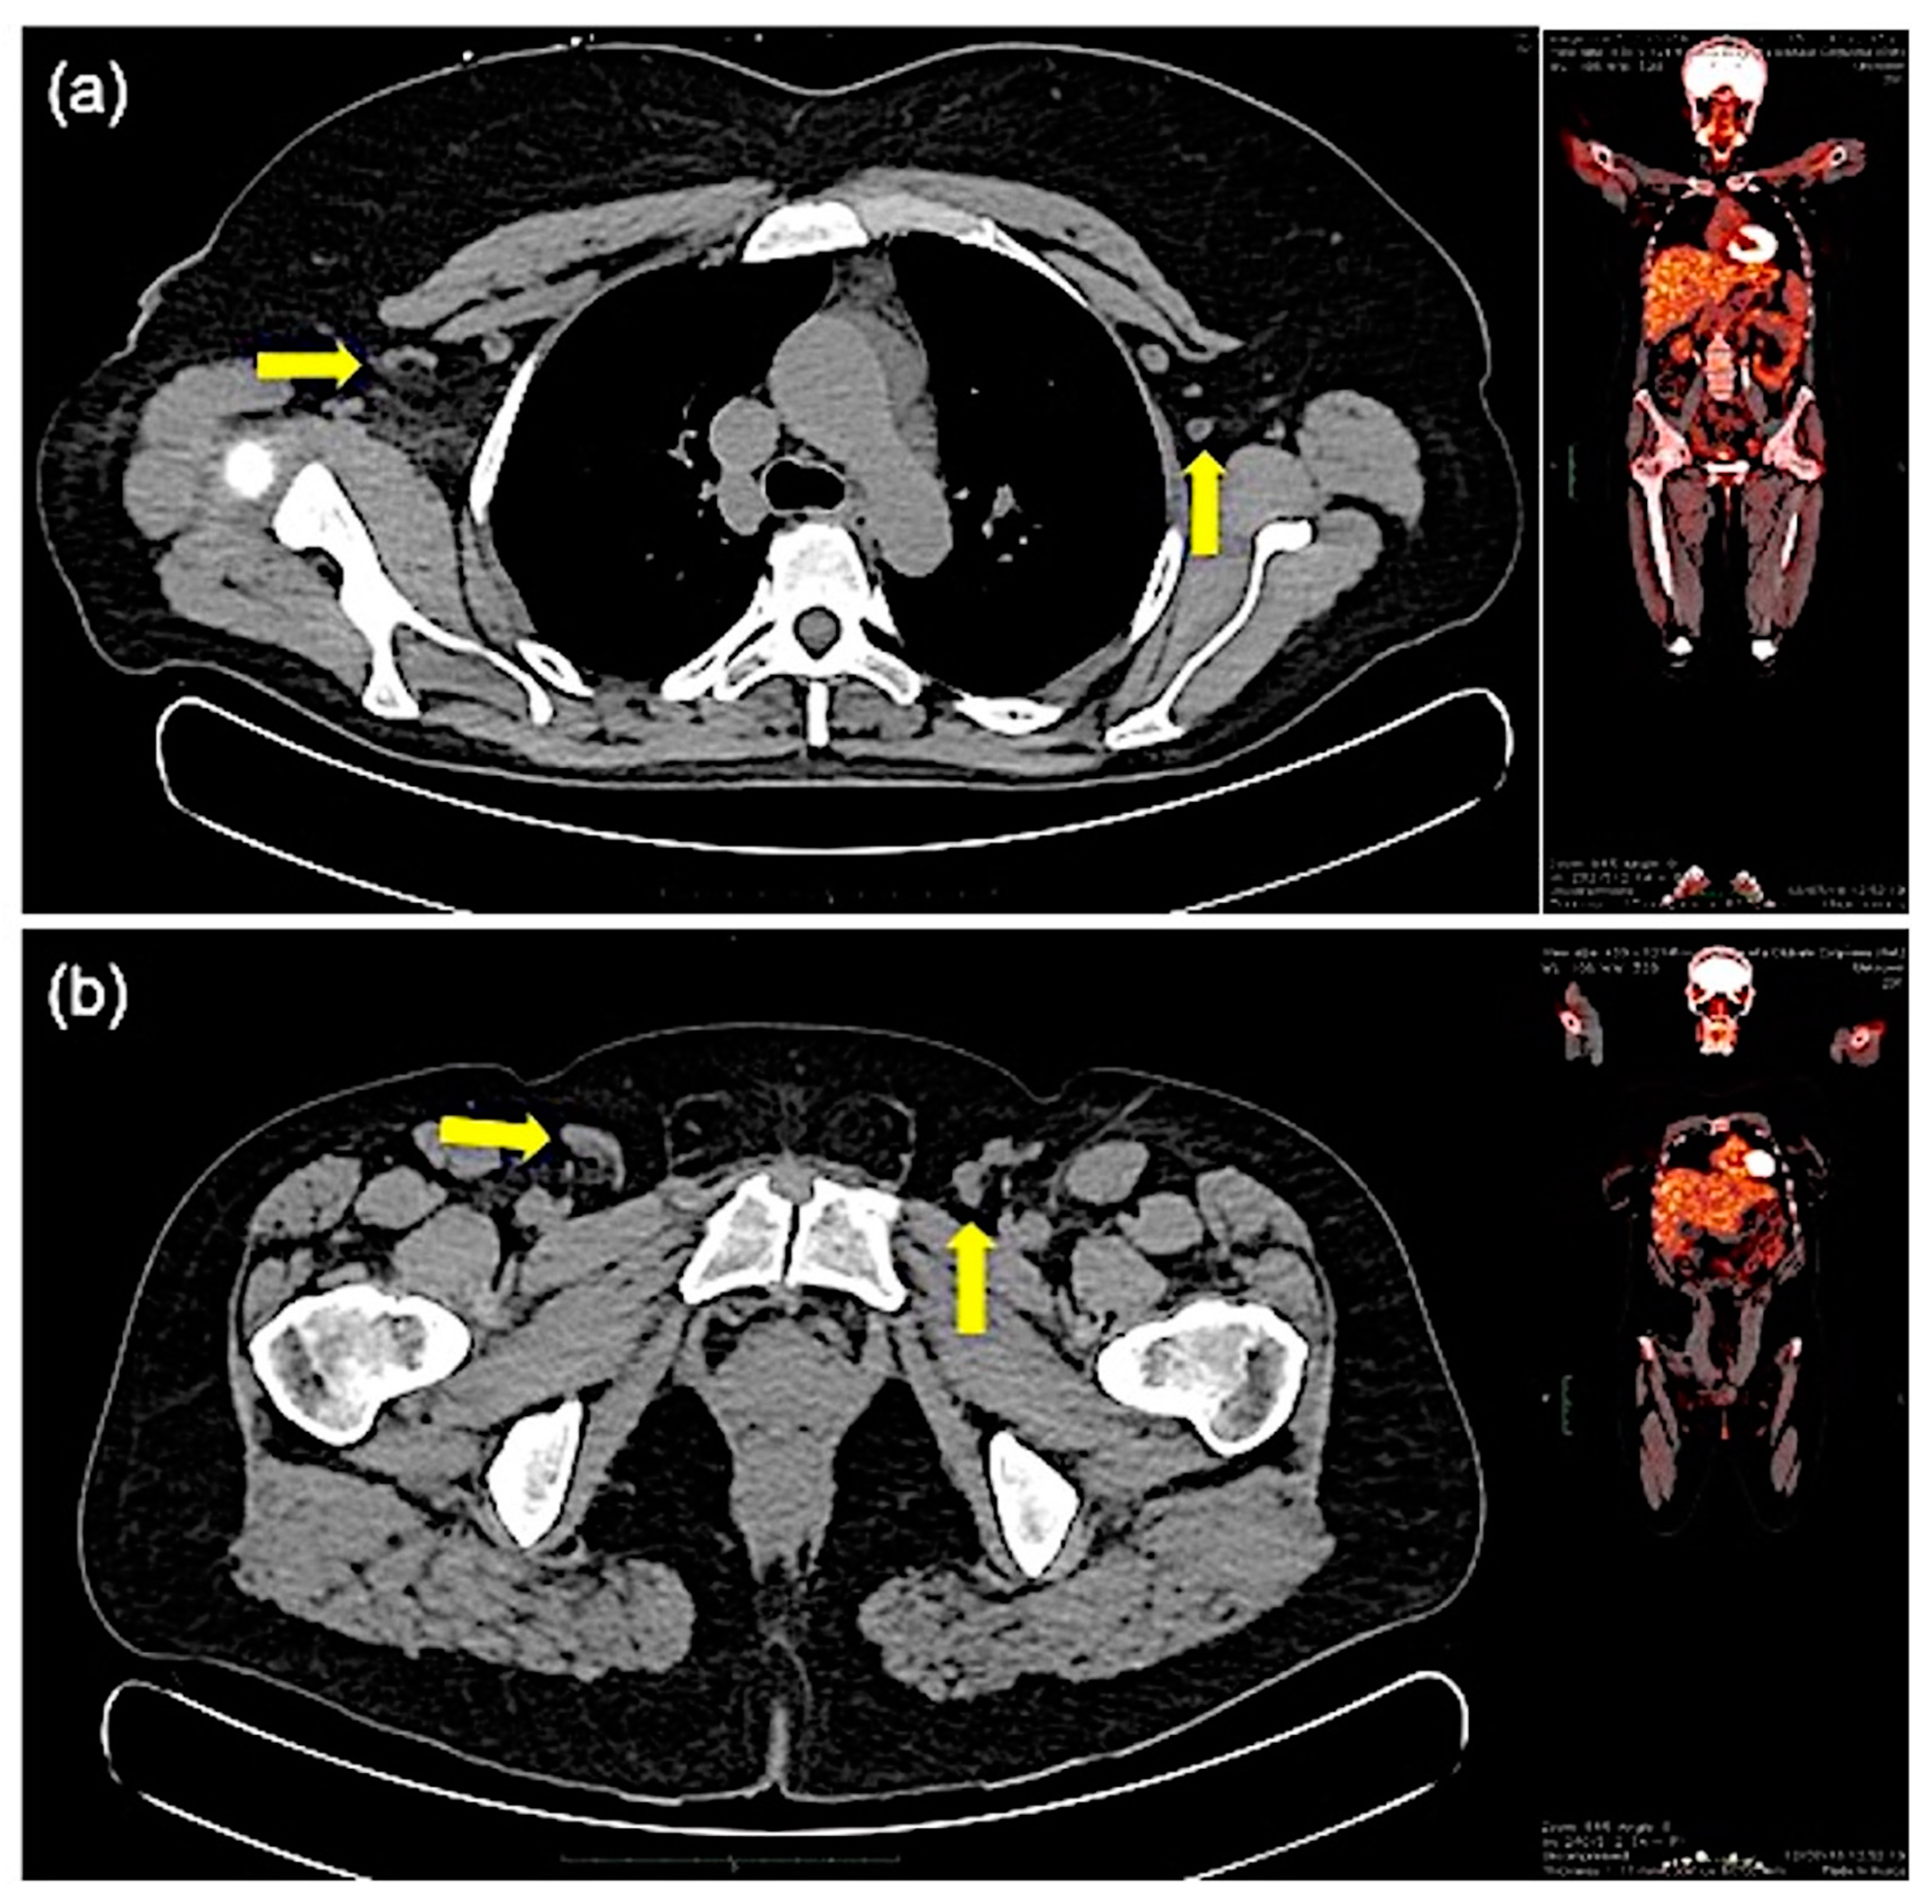

| Symptoms | Angioedema Urticaria Pruritus Periodic weight gain Gastrointestinal symptoms Splenomegaly Lymphadenopathy | - |

| Splenomegaly | 9 (15.7%) | [2,12,20] |

| Lymphadenopathy | 8 (14%) | [12,16] |